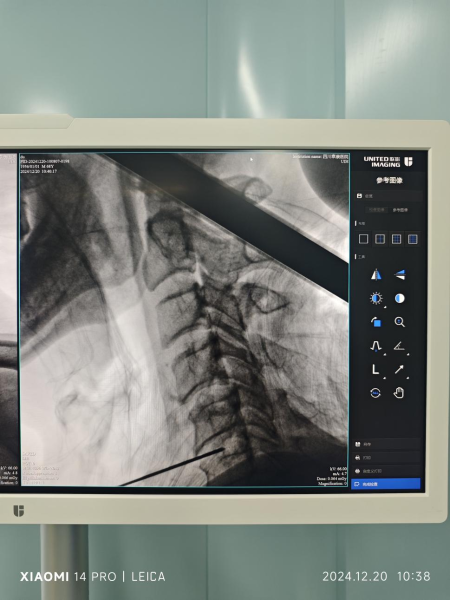

2024年12月20日,骨科李开南主任主刀,在无需麻醉情况下,利用直径0.9 毫米的弹力导针精准穿刺定位颈5/6椎间盘,置入激光光纤,使用2W 970nn激光强度治疗4分30秒后,患者术中当即诉说感到头部昏沉症状得到明显改善及颈肩痛症状也有缓解。术后两天患者基本恢复正常生活,术后一周顺利出院。

(图1,图2患者术中定位)

(图3,图4为术中穿刺定位透视)